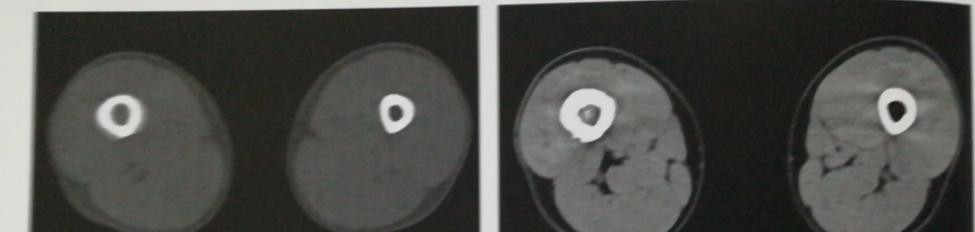

中枢神经系统。CT检查有很高的诊断价值,尤其是对颅内肿瘤、脓肿和肉芽肿、寄生虫病、颅脑外伤、血肿、出血、脑梗死、先天畸形或发育不良、椎管内肿瘤、椎管狭窄、椎间盘突出等疾病有很好的定位和定性诊断,但注意:CT检查对血管畸形有一定限度。